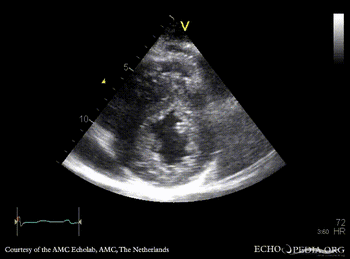

PSAX: severe concentric hypertrophy of left ventricle PLAX with Color Doppler: high velocity turbulent flow in LVOT, moderate mitral regurgitation